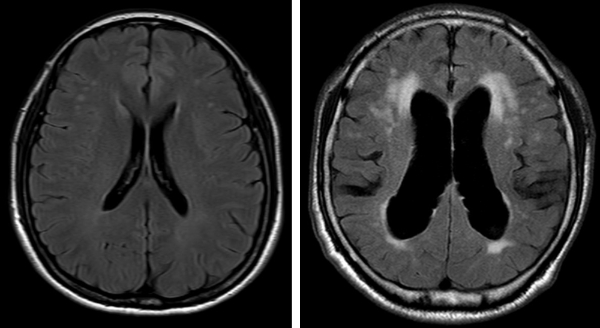

뇌척수액은 뇌실에 존재하는 맥락총이라는 부분에서 생성돼 뇌 주변을 순환한 뒤 거미막 융모에서 흡수 되는데, 생성이 과다하거나 흡수가 잘 되지 않으면 뇌실 내 적정양인 120-150ml를 유지하지 못하고 점점 축적된다.

이러한 상태를 수두증이라고 부른다. 그리고 뇌척수액의 압력이 정상 범위인데도 수두증이 나타나는 것을 정상압 수두증이라고 한다. 과다 축적된 뇌척수액이 뇌 조직을 압박하게 되면 보행·배뇨장애, 기억저하와 같은 증상으로 나타나는 것이다. 단순히 증상만 놓고 보았을 때는 파킨슨병으로 오인하기 쉽다.